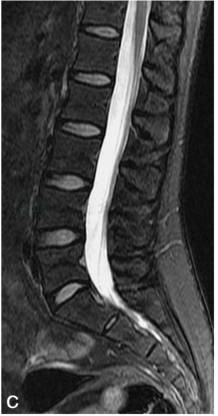

矢状位:显示椎体的连续解剖结构,腰椎呈生理曲度前凸,骶尾椎呈生理性后凸。腰椎椎体呈矩形,椎体边缘骨皮质在T1WI和T2WI上均呈低信号;椎体内随着年龄增长,逐渐由红骨髓向黄骨髓转换,儿童时期主要为红骨髓,T1WI呈低信号,T2WI呈中等信号,随着年龄的增长,椎体内大量脂类或脂肪成分堆积可形成局灶或弥漫性脂肪沉积改变,T1WI呈略高信号,T2WI呈中等信号(图2)。椎体后缘的中间部位有短的条状凹陷,为椎基静脉所致。椎体的附件包括椎弓、椎弓根、椎板、棘突、横突及上、下关节突等,其信号与椎体的信号类似。

图2 正常腰椎MRI图像

A.T1WI;B.T2WI;C.T2WI 脂肪抑制序列椎体松质骨呈中等信号,皮质骨呈低信号,椎体内脂肪沉积呈高信号,脂肪抑制序列呈低信号,脑脊液呈T1为低信号,T2为高信号